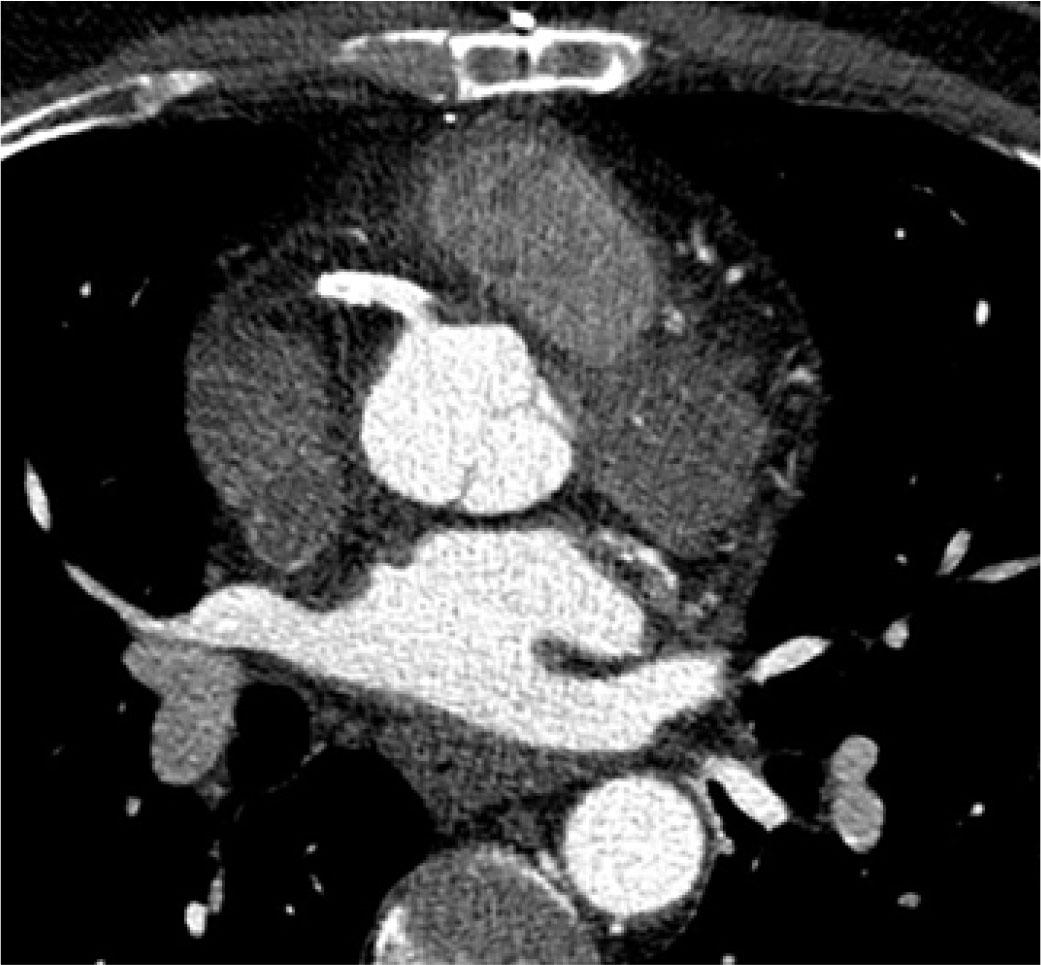

Because the guidewire appeared to be in the false lumen, it was withdrawn and replaced with a 0.014” CHOICE PT Floppy guidewire (Boston Scientific), which was successfully used to cross the lesion. The proximal dissection flap was sealed using a Resolute Integrity drug eluting stent (DES) deployed into the RCA ostium at 16 atm. Afterwards, a buddy wire was used to aid in the delivery of two short Prokinetic Energy 3.5/15 mm (BIOTRONIK) and 3.5/13 mm (BIOTRONIK) bare metal stents (BMS) placed in the distal segment at 14 and 16 atm, respectively. Lastly, a 4.0/38 mm Resolute Integrity stent (Medtronic) was used to cover the culprit lesion and seal off the dissection in the mid-proximal part of the RCA (Figure 3), with a good final angiographic result and restoration of Thrombolysis in Myocardial Infarction (TIMI) grade 3 flow (Figure 4). Final angiography and aortography with pigtail catheter showed complete sealing of the dissection flap. Also, a CT scan conducted two days later showed patent RCA stents with no evidence of dissection (Figure 5). The patient remained asymptomatic on guideline-recommended medication after myocardial infarction and was discharged from the hospital five days later.

Computed tomography with contrast in a transverse section at RCA ostium level shows closed intimal flap, without evidence of false lumen.